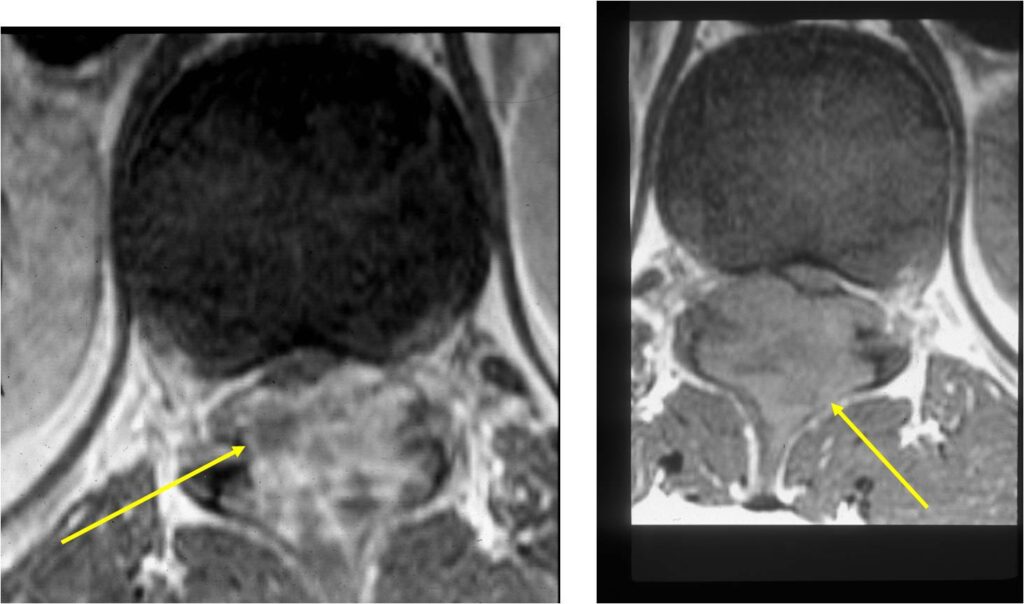

- Spine (40% of cases; usually posterior elements)

MRI:

- Also useful in determining extent

- There is often extensive edema around the tumor in the surrounding bone and soft tissues that can lead to a misdiagnosis of a malignant tumor.

- Spinal lesions may be accompanied by muscle spasms, scoliosis and neurological manifestations